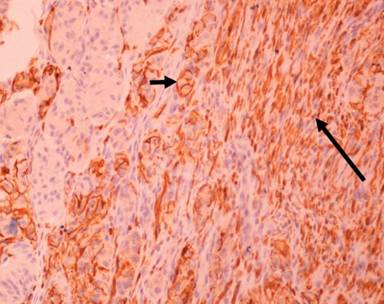

Histologically, it was located in the submucosa (Figure 5), relatively well demarcated without a capsule and with expansive pushing margins. Its stroma was extensively hyalinized. It consisted of epithelioid cells and spindle-shaped cells forming ill defined interlacing fascicles, and dispersed ganglion-like cells amongst them (Figure 6). The epithelioid cells were rather bland, arranged in alveolar, trabecular or rosettes formations, with slight nuclear pleomorphism, and sparse mitoses (less than one per 10 HPF (x200)); no necrosis was evident (Figure 7). Immunohistochemically, epithelioid cells were positive for synaptophysin and chromogranin A (Figure 8). Spindle-shaped cells and ganglion-like cells were found expressing S-100 protein (Figure 9), while epithelioid cells were negative for S-100 protein expression. Combined histopathological and immunohistochemical findings were consistent with gangliocytic paraganglioma.

Figure 8. On immunohistochemical staining, epithelioid cells were positive for chromogranin A, while spindle and ganglion cells were negative (arrow: epithelioid cells). |

Figure 9. Immunohistochemistry for S-100 protein expression detection. Spindle-shaped cells and ganglion-like cells were positive, while epithelioid cells were negative (short arrow : ganglion-like cells; long arrow: spindle-shaped cells). |